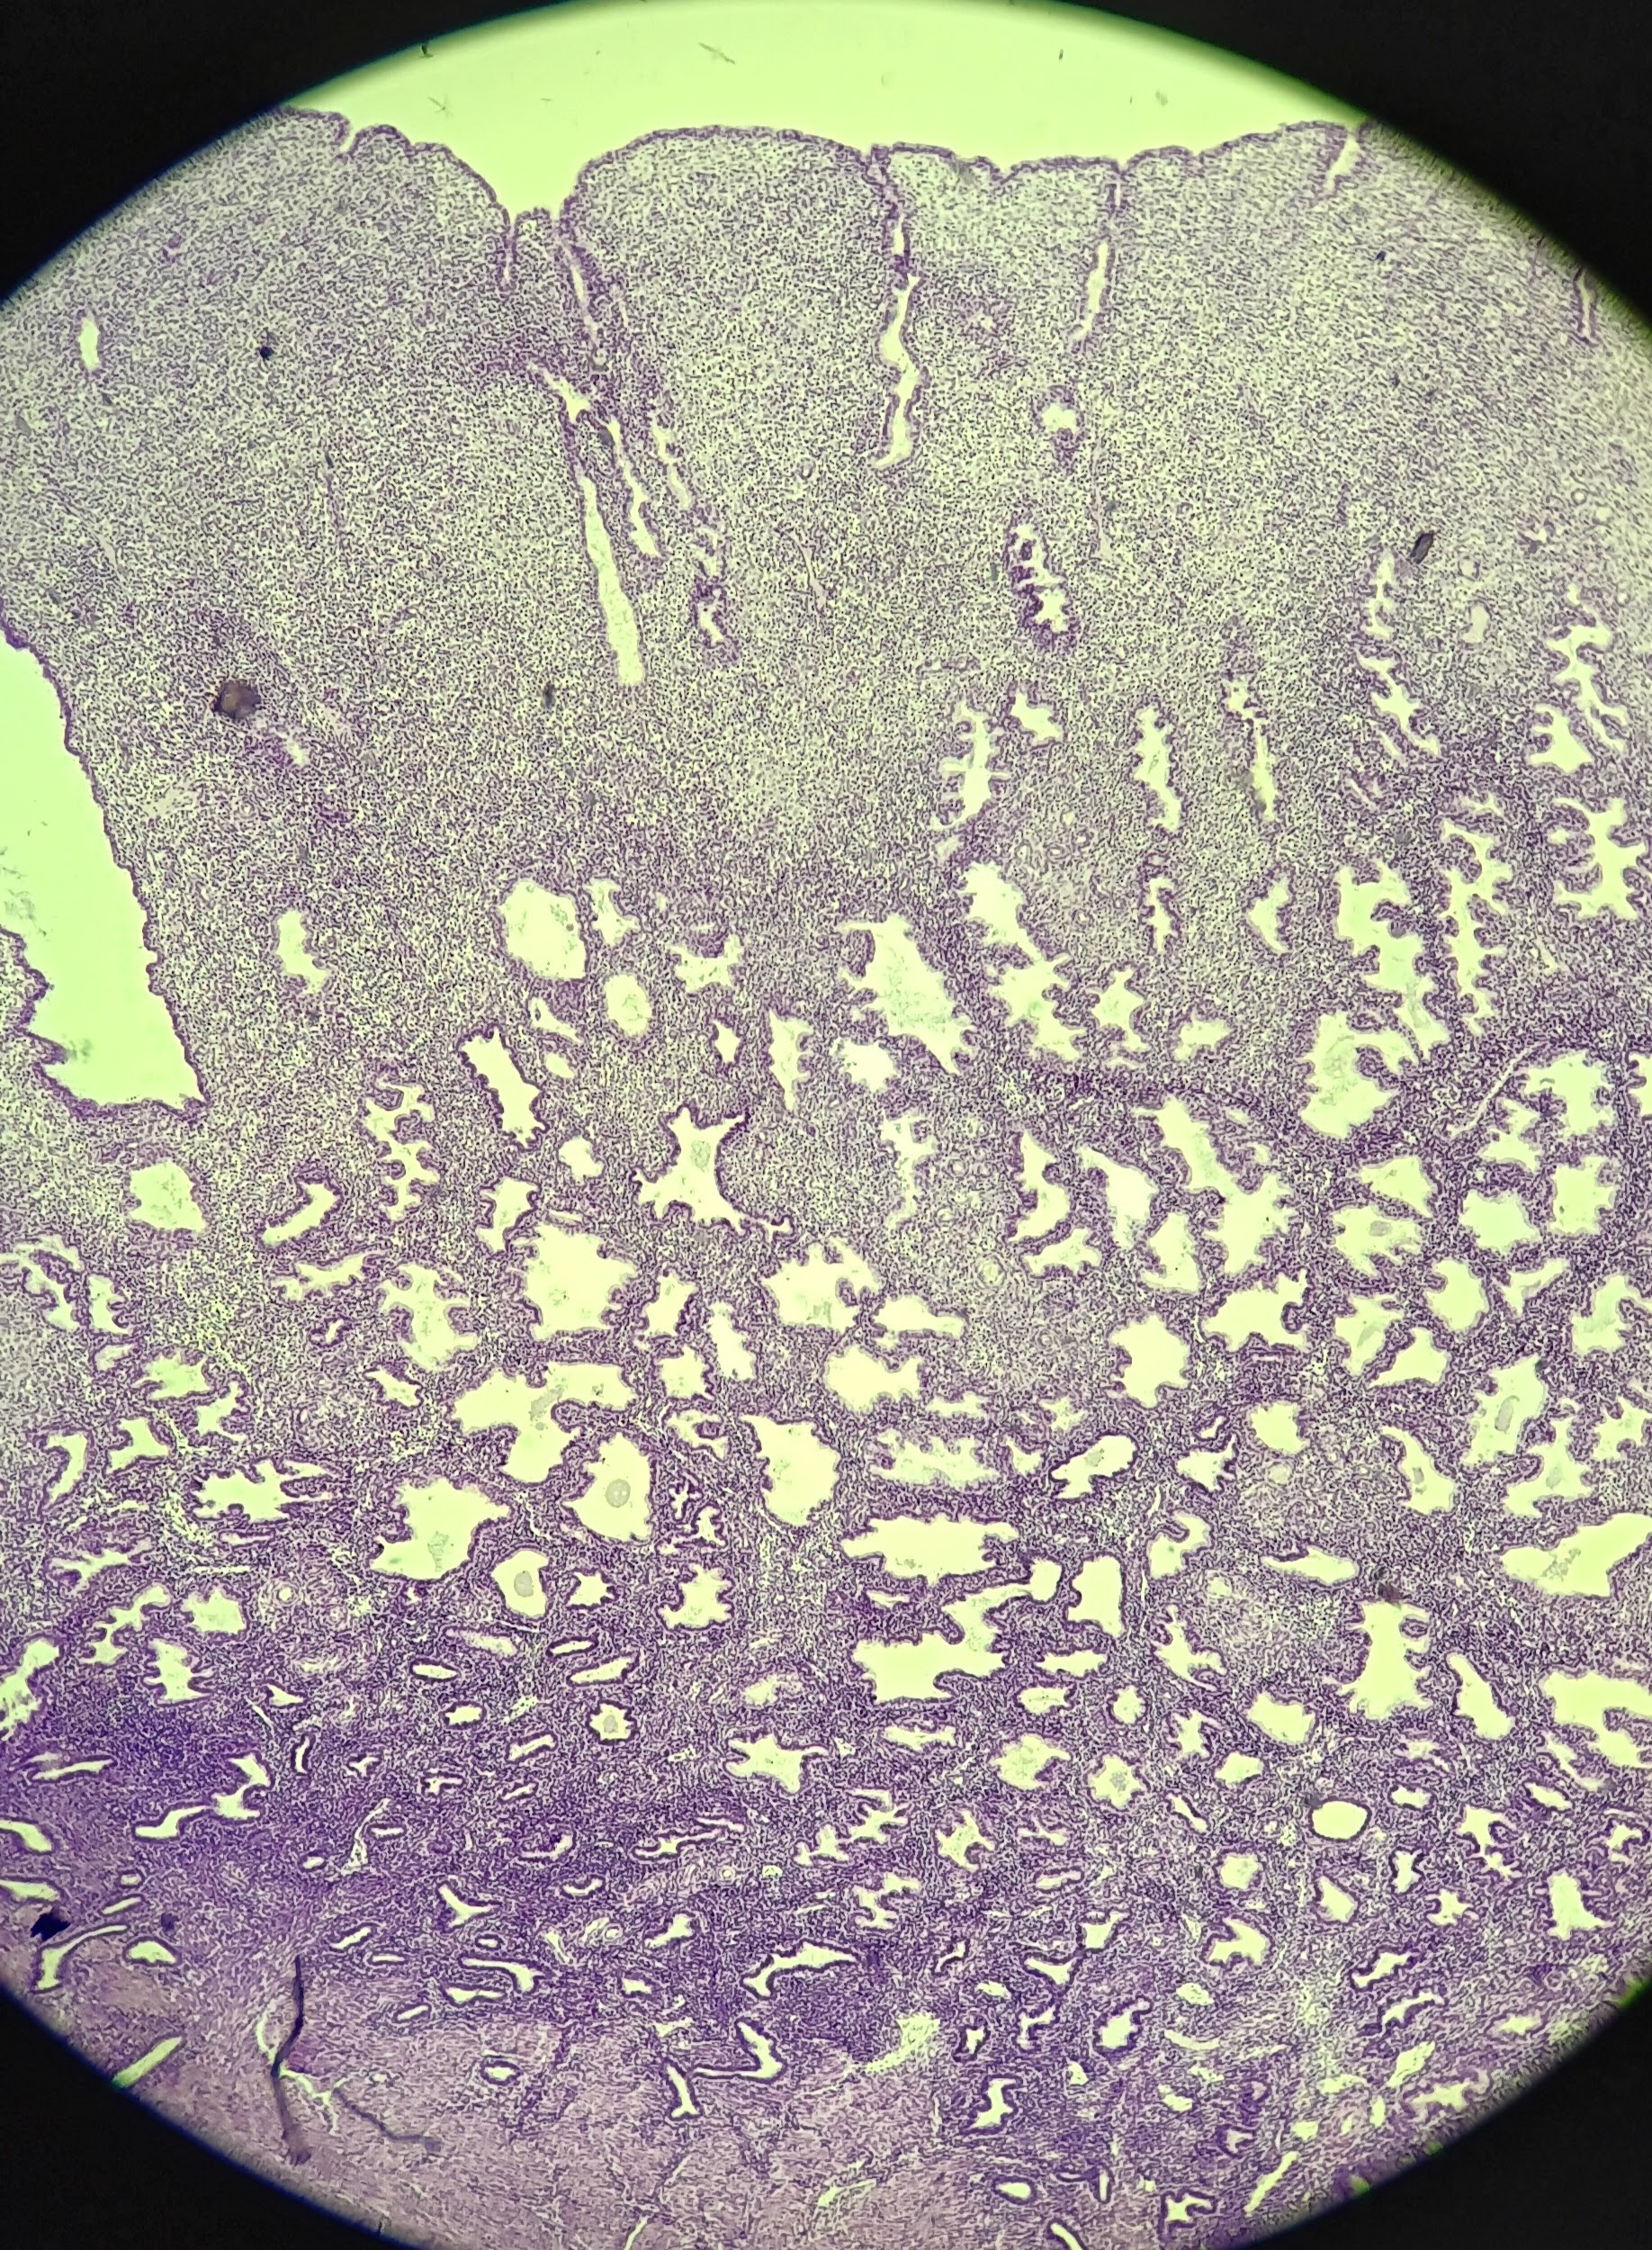

Primordial follicle

1

Primordial follicle

Primordial follicle

1

Primary follicle

2

Primary follicle

Primary follicle

2

Secondary follicle

3

Secondary follicle

Secondary follicle

3

Tertiary follicle

4

Tertiary follicle

4

Mature follicle

5

Mature follicle

Mature follicle

7

Antrum

10

Zona pellucida

9

Theca folliculi

8

Corona radiata